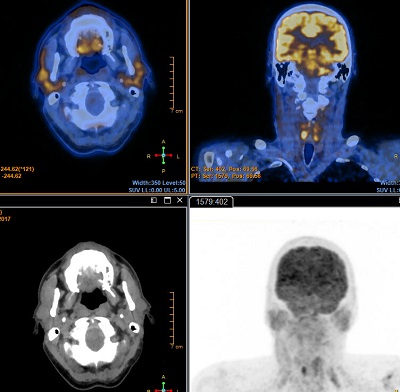

The Automatic Registration Tool allows automated 3D registration of multimodality studies (PET, SPECT, CT and MR). Four registration methods are supported: Mutual information, cross correlation, auto correlation and fiducial matching.